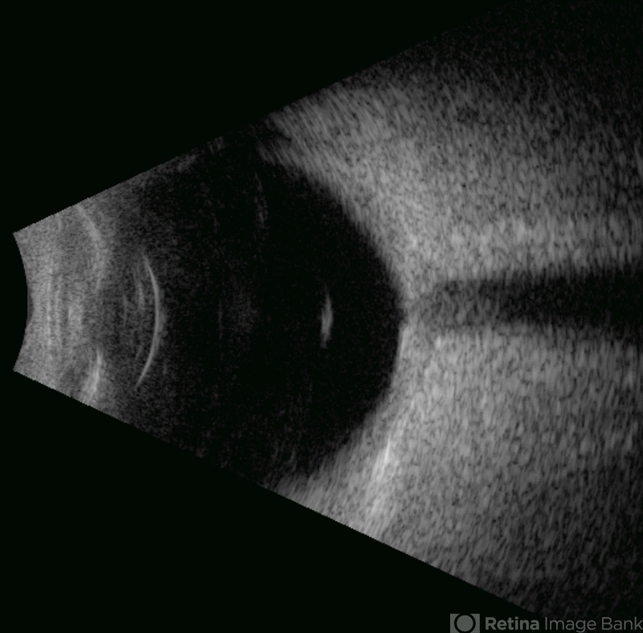

- Ultrasonography device

- This B-mode axial ultrasound scan demonstrates the Weiss ring, visualized as a circular hyperechoic structure in the vitreous cavity, representing the detached posterior vitreous face with the optic disc insertion site. The ring shows mild mobility on dynamic assessment without retinal traction.